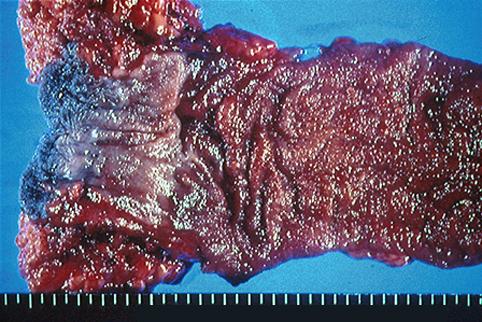

疾病(病理主体)的分类恶性上皮性肿瘤/腺癌

部位(按器官分)大肠/占据大肠的2个以上区域

检查方法切除标本(宏观)

肿瘤的肉眼分类4型(弥漫浸润型)/

肿瘤最大直径40以上

肿瘤的深度ss(a1)